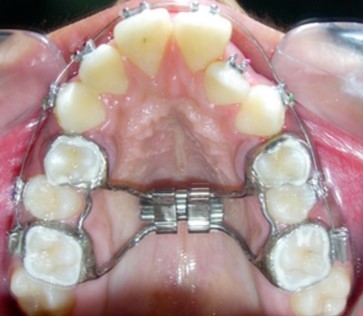

Figure 5.Rapid palatal expansion appliance in situ